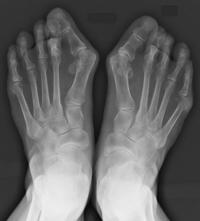

特徴的な症状は、母趾の先が人さし指(第二趾)の方に「くの字」に曲がり、つけ根の関節(MTP関節)の内側の突き出したところが痛みます。その突出部が靴に当たって炎症を起こし、ひどくなると靴を履いていなくても痛むようになります=写真=。

外反母趾の症状としては、見た目の変形以外に痛みが問題になります。母趾の飛び出しを指で押すと痛む、靴を履いたときに痛む、靴を脱いでも痛む-と症状が進みます。